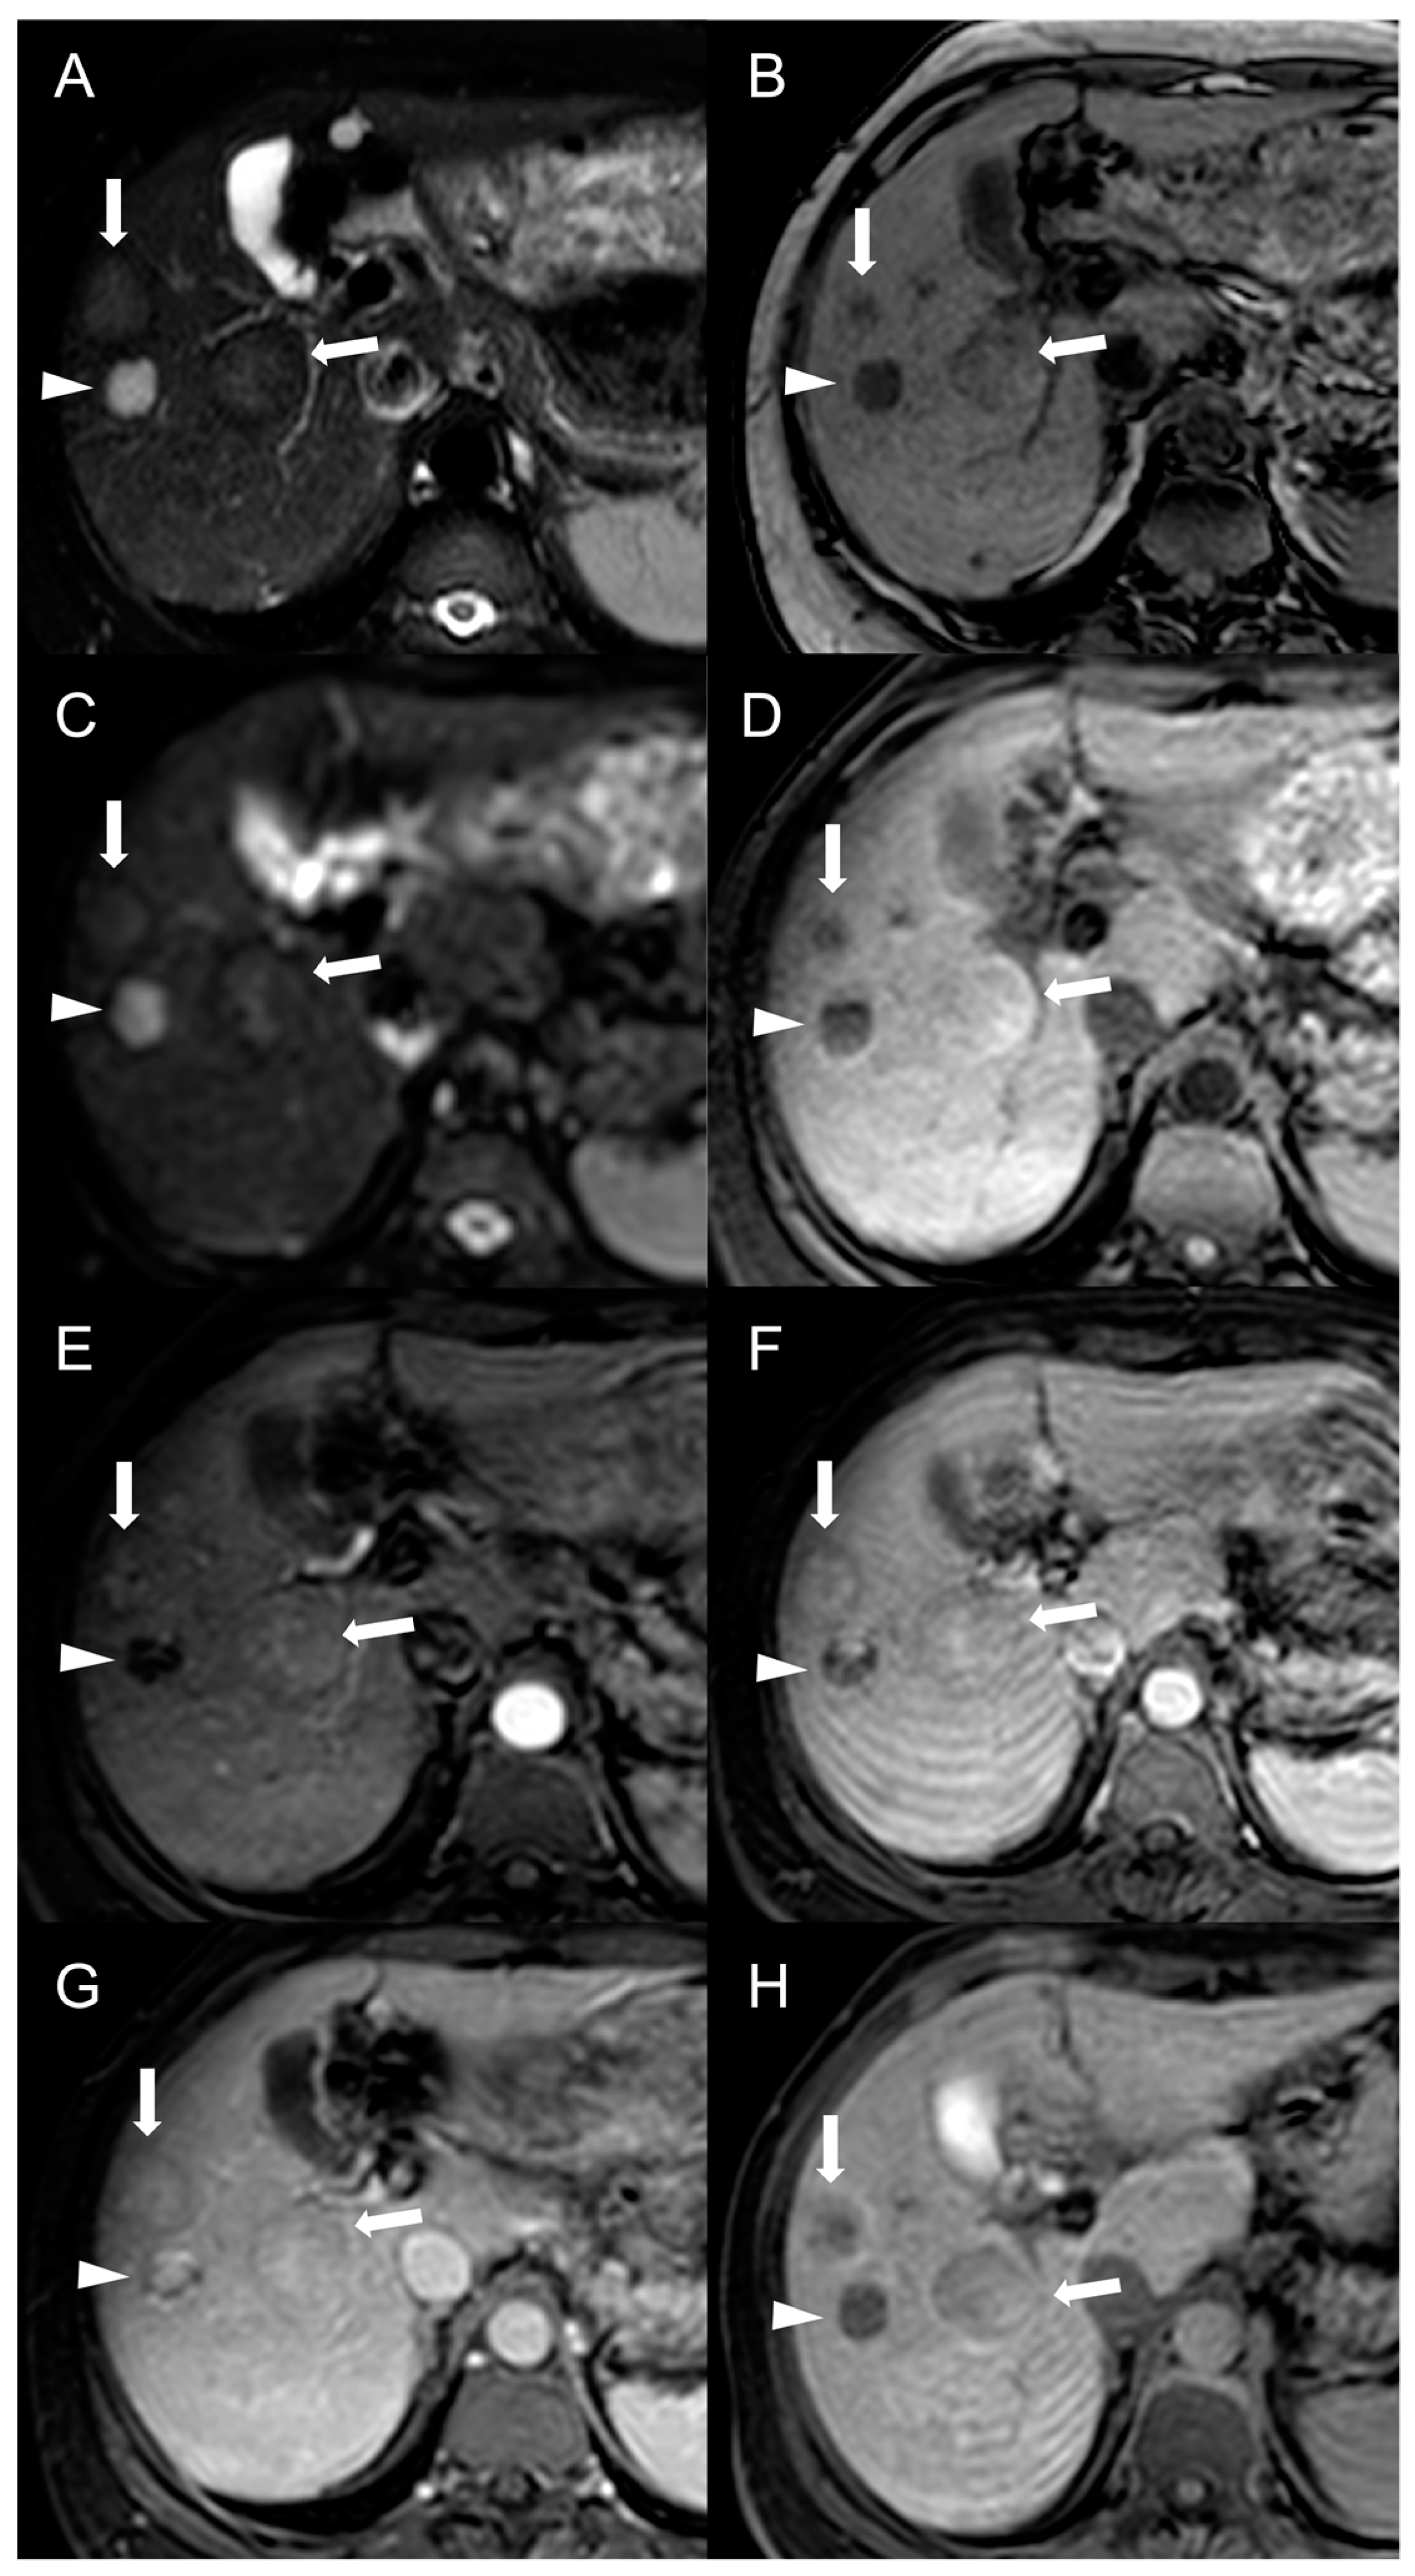

However, considering that approximately 25% of HCCs do not display washout in the portal and delayed phases, while up to one-third of FNH-like RNs can show it, the specificity of this feature for the diagnosis of HCC in BCS is relatively low. As reported by Van Wettere et al. [22], the association of homogeneous APHE and homogeneous washout was identified in one-third of benign lesions and in half of HCC cases. The resulting sensitivity and specificity for diagnosing HCC were 50% and 70%, respectively. When considering the combination of any type of APHE (homogeneous, peripheral or central) and any type of washout (homogeneous or peripheral), a sensitivity of 100% and a specificity of 61% were achieved. For this reason, given the risk of an unacceptable rate of false-positive results, the LI-RADS and AASLD/EASL criteria for the non-invasive diagnosis of HCC cannot be applied in BCS patients [28,29,30]. The differential diagnosis between FNH-like RNs and HCC becomes even more challenging due to the potential for the former to increase in size and/or in number. Therefore, it is important to consider additional features supportive of diagnosis of HCC, such as T1 hypointensity, hyperintensity in T2-weighted and high b-value DWI, and absence of a central scar on MRI [42], as shown in Figure 6.

Figure 6.

MRI examination of a 67-year-old female patient with Budd–Chiari syndrome reveals a new focal lesion of 13 mm in the left lobe (arrow). The lesion appears hyperintense on T2-weighted images (A), hypointense on T1-weighted images (B,D) and shows restricted diffusion in high-b-value DWI (C). After contrast agent administration, the lesion demonstrates marked enhancement on T1-weighted arterial phase images (E), followed by central washout with enhancing capsule on T1-weighted portal venous (F) and delayed (G) phases. On T1-weighted images in the hepatobiliary phase (H) the lesion shows a hypointense signal, suggesting a diagnosis of HCC. Perihepatic ascites (asterisks) can be observed on T2-weighted images (A) and DWI (C).

Hepatobiliary contrast agents provide valuable help in the differential diagnosis, as HCC most often demonstrates a hypointense signal in HBP. In the above-mentioned study [22], the combination of this feature with APHE and washout proved effective in distinguishing all HCC lesions from FNH-like RNs. Indeed, benign regenerative lesions typically appear isointense-to-hyperintense compared to the normal liver in HBP, regardless of the presence of washout on portal venous or delayed phase images.